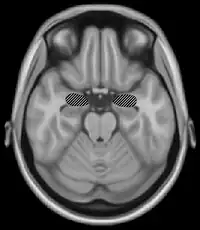

Many neuroimaging studies have found evidence of the importance of right secondary auditory regions in aspects of musical pitch processing, such as melody.[10] Many of these studies such as one by Patterson, Uppenkamp, Johnsrude and Griffiths (2002) also find evidence of a hierarchy of pitch processing. Patterson et al. (2002) used spectrally matched sounds which produced: no pitch, fixed pitch or melody in an fMRI study and found that all conditions activated HG and PT. Sounds with pitch activated more of these regions than sounds without. When a melody was produced activation spread to the superior temporal gyrus (STG) and planum polare (PP). These results support the existence of a pitch processing hierarchy.